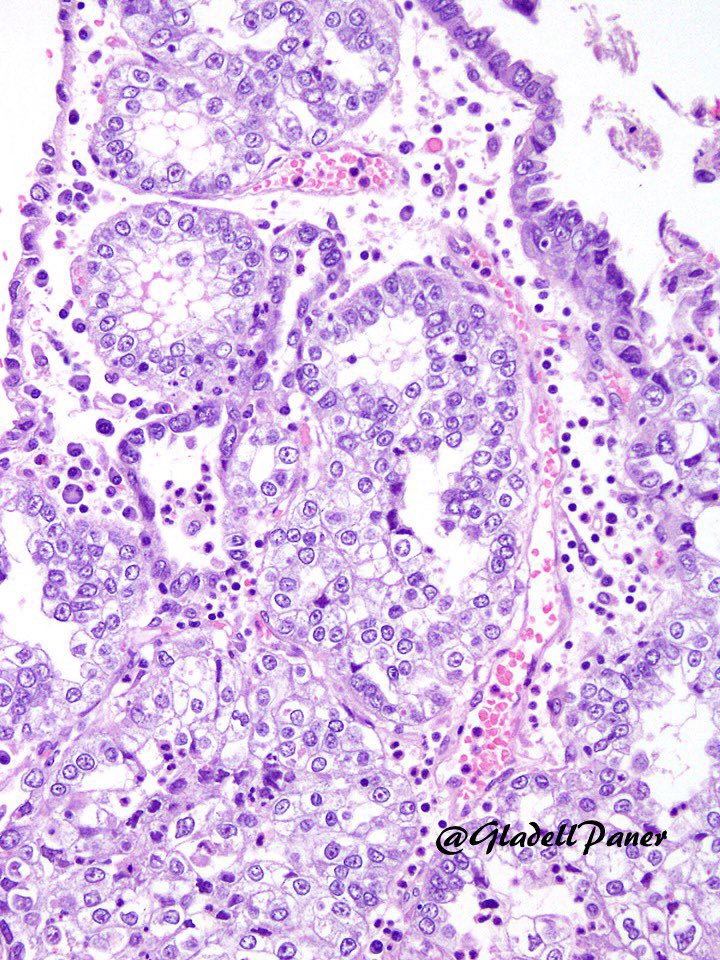

4.3 cm renal mass confined to kidney, tumor cells are predominantly with proliferative, tubular pattern 🎨 CK7 positive (strong, diffuse) 🎨 CD117 negative Thoughts? Sean R Williamson MD Kiril_T_Can Michelle_Hirsch (Donovan) Priya Rao, MD Ankur Sangoi

Kidney, young F adult #gupath Dr. Luca Olaleke Folaranmi Aurélien Morini, MD, MSc 🇫🇷🇪🇺💙💛 Celina Stayerman MD 🔻Nusrat Zahra🔻🇵🇸 @miss_me1986 Gonzalo De Toro Tristan Rutland MBBS FRCPA IFCAP Anandi Lobo, MD Sumanta Das Lorand Kis Erik Kouba bansar Carlos Miguel Ruiz Carlos Nieves Padma Priya J Susan Prendeville @AkgulMd Ankur Sangoi Barry McGinn